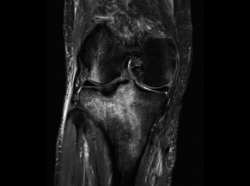

4.3. Osteocondritis

En la osteocondritis se aprecia una lesión subcondral caracterizada por resorción ósea, colapso y la formación de un secuestro.

El estudio por RM es una herramienta valiosa para diagnosticar e identificar las lesiones del cartílago. Conocer el aspecto del cartílago y saber cuánto y cuándo se lesiona, basándose en las clasificaciones actuales, permiten al radiólogo proporcionar la máxima información al clínico(20).

Numerosos estudios demuestran la utilidad de la RM para definir la estabilidad o inestabilidad de la lesión en la osteocondritis, destacando su carácter no invasivo y la capacidad de valorar la progresión y la respuesta al tratamiento(21) (Figuras 53 y 54).

Figura 53. Corte de secuencia sagital (A) y axial (B) T2 Fat-Sat de RM de rodilla: lesiones osteocondrales en el fémur y la rótula.

Figura 54. Corte de secuencia T1 y T2 Fat-Sat coronal de resonancia magnética: gran osteocondritis en el cóndilo femoral interno con edema en la medular adyacente.